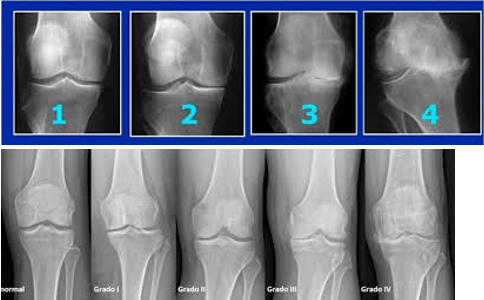

• Radiografías: identifican disminución del espacio articular, osteofitos y esclerosis ósea

La clasificación del grado de artrosis permite definir el tratamiento más adecuado.